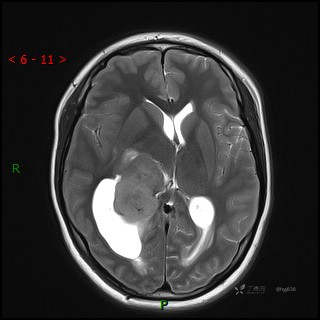

辅助检查:CT MRI

临床诊断:脑室占位

颅脑CT平扫

MRI平扫